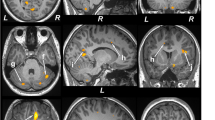

Anatomical Landmarks

The axial slice showing the most anterior extent of the anterior margin of the genu of the corpus callosum was chosen as the reference image on which to center the voxels for both locations (Kumar et al, 2002). This was determined by placing a cursor at the anterior margin of the genu in the midline, on several axial slices through the genu. The slice showing the most anterior location of the anterior margin of the genu was then chosen as the reference slice. This anatomical landmark was chosen because it is an identifiable single location, which helps standardize voxel placement, despite variations in scanning angle. Other potential single location sites in the brain are at a greater distance from the areas of interest, and therefore the potential error, due to variation in scanning angle, is greater. This slice corresponds to a level 10 mm superior to the AC-PC line, though variations in head size will subtly impact the precise location.

Dorsolateral prefrontal cortex

The medial border of the voxel is placed contiguous to the gray–white juncture on the medial side of the hemisphere using the same reference slice as above. The posterior boundary of the voxel is placed immediately adjacent to the anterior margin of the frontal horn of the lateral ventricle.

Subcortical voxel

The mesial border of the voxel is at the junction of the head of the caudate nucleus and the lateral ventricle. The posterior boundary does not extend below the inferior tip of frontal horn of the lateral ventricle (Figure 2). Note that voxels placed in the subcortical nuclei region were occasionally taken from one or two slices below the slice displayed in the figure where it was better visualized.